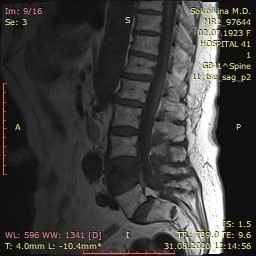

Пролабирование l5 s1

Пролабирование l5 s1 114 фотографий